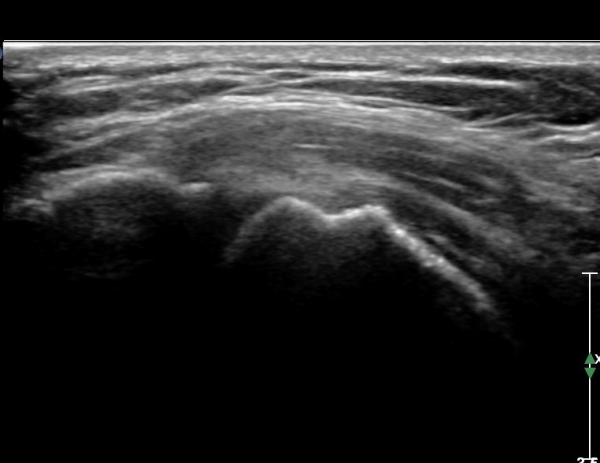

ŽÃËÀÚ¸¦ ¾à°£ ¿ÜÃøÀ¸·Î À̵¿ÇÏ¿© Á¶ÀýÇÏ´Ï À̵ιڰÇÀÌ °üÂûµÇ°í(»çÁø 6) ¾à°£ ¸»´ÜÀ¸·Î À̵¿ÇÏ´Ï °ÇÁÖÀ§ ¼ö¾×Àú·ù°¡ °üÂûµÈ´Ù(»çÁø 7). Á߸³À§¿¡¼ ŽÃËÀÚ¸¦ ¾î±ú ¿ÜÃø¿¡ ´ë°í °ßºÀ°ú ´ë°áÀýÀÌ ¸ðµÎ º¸À̵µ·Ï Á¶ÀýÇÏ¿© ¿ÜÀüÇÏ¸é¼ Ãæµ¹ ¿©ºÎ¸¦ °üÂûÇÑ´Ù. Á¤Áö »óÅ¿¡¼ ´ë°áÀýÀÇ °ñ °á¼ÕÀÌ °üÂûµÇ¾î ¸¸¼ºÀûÀÎ Ãæµ¹À» ½Ã»çÇÑ´Ù(»çÁø 8). ¿ÜÀü½Ã »ó¿Í°ñµÎ°¡ »ó¹æÀ¸·Î ¿òÁ÷ÀÌ°í °ßºÀ°ú Ãæµ¹ÇÔÀÌ °üÂûµÈ´Ù(»çÁø 8, ÷ºÎµ¿¿µ»ó 1).

±ØÇ졂 Á¾´Ü¸é °Ë»ç¿¡¼ Àá¾×³¶³» ¼ö¾×Àú·ù°¡ °üÂûµÇ°í(»çÁø 9) ÅÒÃËÀÚ¸¦ Á¶±Ý ³»ÃøÀ¸·Î À̵¿ÇÏ´Ï ±Ø»ó°ÇÀÌ ¼Ò½ÇµÇ°í ¼ö¾×Àú·ù°¡ °üÂûµÈ´Ù(»çÁø 10).

ȸÀü±Ù°³ Ⱦ´Ü¸é°Ë»ç¿¡¼ ±Ø»ó°Ç ³»ÃøºÎ ºÎºÐ °á¼ÕÀÌ °üÂûµÇ°í(»çÁø 11) ŽÃËÀÚ¸¦ Á¶±Ý ¸»´ÜÀ¸·Î À̵¿ÇÏ´Ï ±Ø»ó°Ç ³»ÃøºÎ ÀüÃþÆÄ¿ÀÌ °üÂûµÈ´Ù(»çÁö 12).